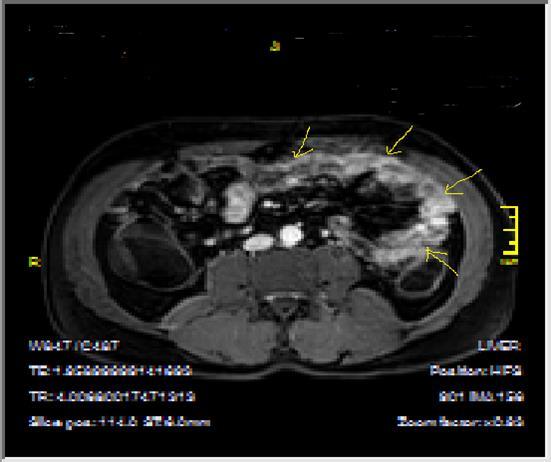

Figure 2a.Concentric luminal narrowing, mural and transmural involvement of terminal ileum due to Crohn’s disease in T2W coronal sequence after OCA application.

Figure 2b.Curvi-lineer, diffuse peripheral enhancing bowel wall in the terminal ileum on axial T1W post-contrast image.